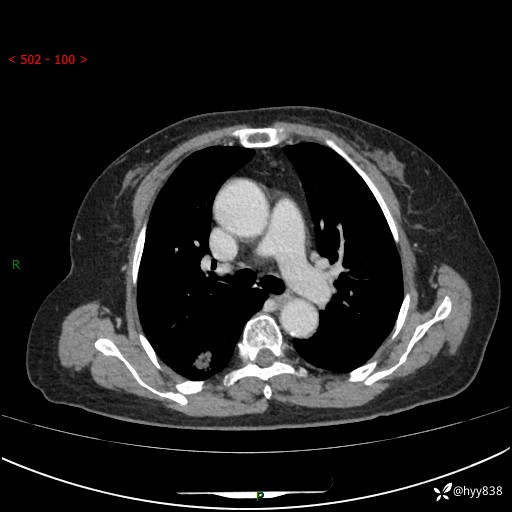

71岁/女,发现肺结节1月。偶然发现孤立肺结节,邻近叶间裂凹陷---结果公布(再回首)

【患者信息】:71岁/女

【主诉】:发现肺结节1月

【现病史及既往史】:2024年9月患者因“胆囊结石”于我院肝胆外科住院,期间完善胸部CT提示:右下肺结节灶,高危结节?感染?,病程中无畏寒发热,无咳嗽、咳痰,无活动后气短,无心慌胸闷,无胸痛、咯血,无头晕头痛,无腹痛腹泻,无四肢肌肉酸痛等不适,当时建议其择期复查。今日患者为求进一步复查就诊于我院,完善胸部CT提示:右肺结节,较前一致,遂门诊“肺部结节”收入我科。 自本次起病以来,患者精神、饮食、睡眠可,大小便正常,体力、体重未见明显异常。

【检查】:胸部CT平扫+增强